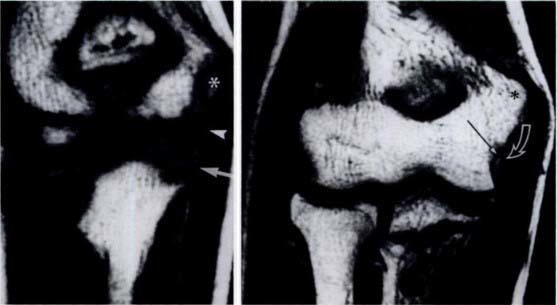

肘部图像。左侧图像(10 岁男孩)中,生长板尚未融合。右图(15 岁男孩),生长板已经融合。图片来源:RSNA/放射学

骨骼尚未发育成熟的儿童都有生长板,生长板是由软骨构成的骨骼区域,软骨是一种橡胶弹性结缔组织,可使骨骼随着年龄的增长而生长并改变形状。生长板比周围的肌肉和骨骼薄弱,容易受伤,可能导致可逆的变化或永久性畸形。

当生长板闭合,不再制造骨骼(或生长)时,骨骼就成熟了。这通常发生在青春期结束时,女孩一般在 13-15 岁左右,男孩一般在 15-17 岁左右。